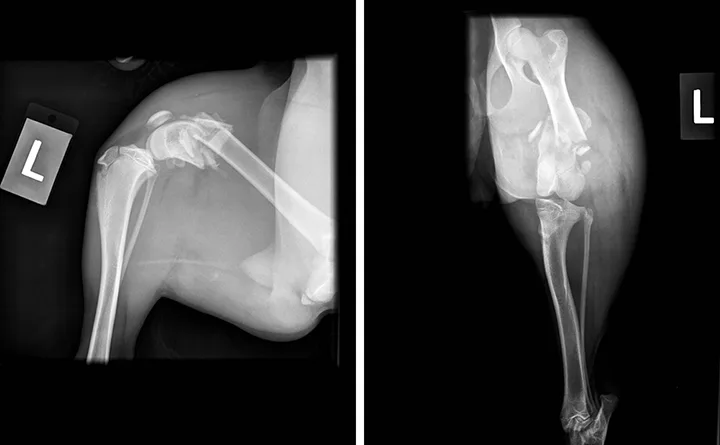

Hematocrit, total protein, and blood urea nitrogen values (obtained via dipstick) were 46%, 6 g/dL (60 g/L), and 5 to 15 mg/dL (1.78 to 5.36 mmol/L), respectively. Of note, if a patient remains hospitalized for more than 24 hours before fracture repair, hematocrit and total protein should be measured again on the day of surgery, as long bone fractures can be an important source of blood loss and consequent anemia. Abdominal-focused assessment with sonography for trauma (ie, aFAST) examination and thoracic radiographs disclosed no abnormalities. Pelvic radiographs showed a closed comminuted fracture of the distal left femur (Figure).

Mediolateral (left) and craniocaudal (right) radiographs of the left pelvic limb showing a comminuted fracture of the distal left femur. At least one transverse oblique fracture crosses the distal third of the femoral diaphysis. The distal fragment is displaced caudoproximally. A few bone fragments are visible near the fracture. The surrounding soft tissue is markedly enlarged in a circumferential pattern around the femur. No soft tissue gas, which would suggest an open fracture, is apparent.